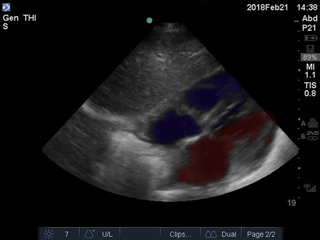

Colorized Atlas - Subxiphoid - Colorized 1

Subxiphoid view Red: Lumen of left atrium and ventricle, Blue: Lumen of right atrium and ventricle Images: Dr. Lindsay Davis, Dr. Hannah Kopinski. Image Editing: Michael Amador and Dr. Matthew Riscinti